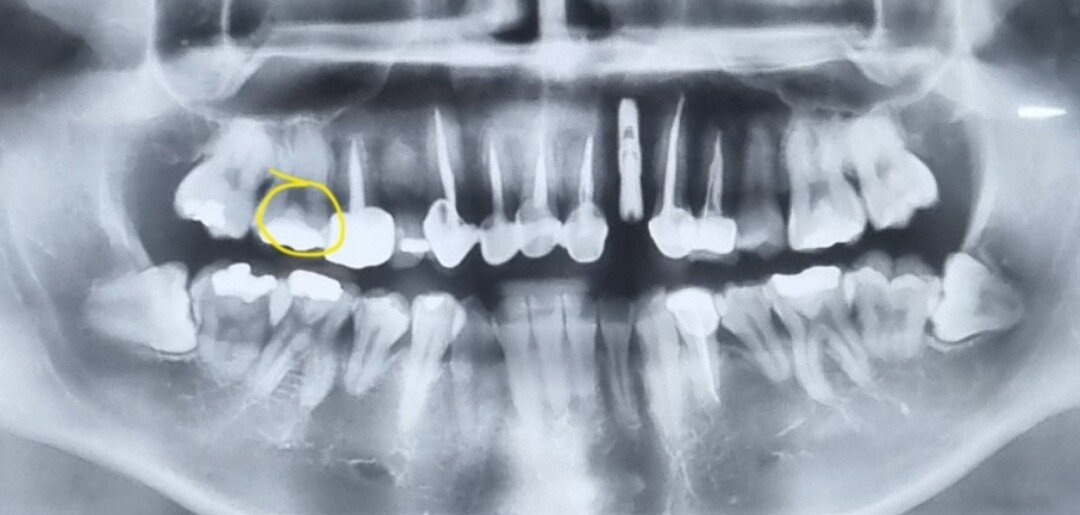

저 동그라미에 크라운 하나 새로 박아야할듯 ㅋㅋㅋㅋ

어릴때 관리를 못받기도했고 얀치도 안하기는 했음.....

엄마는 지금 임플하나 진행중

아빠는 40대부터 틀니착용함

난 23살

누나 2명있는데 누나는 크라운 2,3개 있음 ㅋㅋㅋ

내가 관리를 ㅈ 같이 못한거임?

아니면 그냥 나만 유독 유전이 ㅈ 같은거임?

올해초에 급하게 특약 다 때려놓고 보함 가입함..